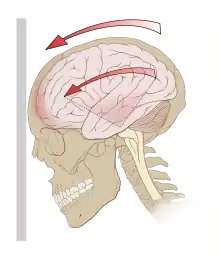

| Acceleration (g-forces) can exert rotational forces in the brain, especially the midbrain and diencephalon. | |

The brain is surrounded by cerebrospinal fluid, which protects it from light trauma. More severe impacts, or the forces associated with rapid acceleration, may not be absorbed by this cushion.[40] Concussions, and other head-related injuries, occur when external forces acting on the head are transferred to the brain.[41] Such forces can occur when the head is struck by an object or surface (a 'direct impact'), or when the torso rapidly changes position (i.e. from a body check) and force is transmitted to the head (an 'indirect impact').[41]

Forces may cause linear, rotational, or angular movement of the brain or a combination of them.[37] In rotational movement, the head turns around its center of gravity, and in angular movement, it turns on an axis, not through its center of gravity.[37] The amount of rotational force is thought to be the major component in concussion[42] and its severity.[43] As of 2007, studies with athletes have shown that the amount of force and the location of the impact are not necessarily correlated with the severity of the concussion or its symptoms, and have called into question the threshold for concussion previously thought to exist at around 70–75 g.[44][45]

The parts of the brain most affected by rotational forces are the midbrain and diencephalon.[46][4] It is thought that the forces from the injury disrupt the normal cellular activities in the reticular activating system located in these areas and that this disruption produces the loss of consciousness often seen in concussion.[4] Other areas of the brain that may be affected include the upper part of the brain stem, the fornix, the corpus callosum, the temporal lobe, and the frontal lobe.[47] Angular accelerations of 4600, 5900, or 7900 rad/s2 are estimated to have 25, 50, or 80% risk of mTBI respectively.[48]